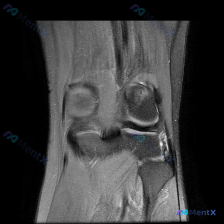

刚整理完一份踝关节MRI读片资料,病灶很典型,分享一下读片思路给大家参考。 病例核心影像信息 影像为踝关节冠状位T2加权单帧图像,清晰度可,主要发现如下: 1. 核心异常:距骨穹顶内侧可见局灶性不均匀T2高信号,边界相对清晰,提示该区域骨髓水肿;距骨穹顶关节面不连续,软骨下骨质轮廓稍不平整,信号增高...